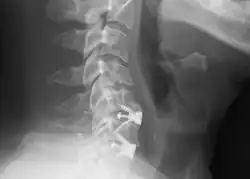

X-rays of anterior cervical discectomy and fusion, C5C6 and C6C7. Lateral view.

To prevent the vertebrae from collapsing and to increase stability, the open space is often filled with a graft. That can be a bone graft, taken from the pelvis or cadaveric bone; or an artificial implant.[4] The slow process of the bone graft joining the vertebrae together is called "fusion". Sometimes a titanium plate is screwed on the vertebrae or screws are used between the vertebrae to increase stability during fusion, especially when there is more than one disc involved.